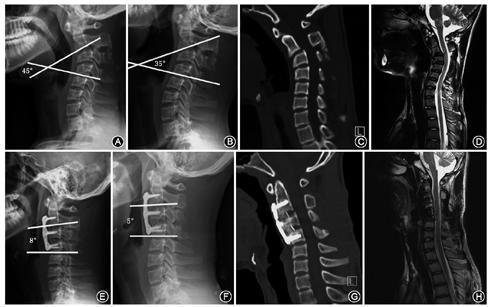

1例患者C2/3分割不全,C3半椎体畸形,仰伸位复位未达到50%,行平衡悬吊牵引未继续复位,行前路C3椎体次全切除,钛网植骨融合,钛板内固定术。

1例患者C2-4先天融合,C2-4后凸畸形。仰伸位无明显复位,一期C3/4椎板切除,C2及C5椎弓根钉固定,后凸矫形,植骨融合术。

1例患者C2-5先天分割不全,C2-5后凸畸形。仰伸位无明显复位,颈后路C2椎板切除,C2-5关节突松解,颈前路C3/4椎体次全切除,C2-5钛板固定,再次翻身行C2-4侧块固定植骨融合。手术需要变动两次体位,注意MEP脊髓监测变化。

患者术后进行3个月、6个月、1年及2年随访,最长随访时间7年,8例患者随访6~84个月,平均36个月。随访时行X线及CT、MRI检查,末次随访时显示均获得骨性融合。8例患者术前后凸区域中立位Cobb角为45°~92°,平均为67°±18°。4例诊断为椎体发育不良患者中有3例术前均行牵引预矫形,预矫形率超过50%,另外1例仰伸位X线示后凸矫形率超过50%。未进行牵引预矫形,一期后路手术。1例诊断为C3-6椎间盘突出,C2棘突过长,颈椎后凸畸形患者,仰伸位X线矫形率未达到50%,牵引后由于C2棘突过长影响后伸无进一步复位遂行颈后路软组织松解C2过长棘突切除,然后前路手术。另外3例诊断为颈椎分割不全,半椎体畸形及椎体先天融合患者,仰伸位X线无明显复位,均一期前路,后路或前后路联合手术。术后出院前中立位Cobb角为0°~23°,平均为8°±8°,较术前显著改善(t=8.471,P<0.05)。末次随访中立位Cobb角为0°~26°,平均为12°±6°,术后矫形率为66%~100%,平均为87%±13%。JOA评分由术前(11.1±2.7)分改善至术后(14.0±1.5)分(t=-2.656,P<0.05)(表1)。